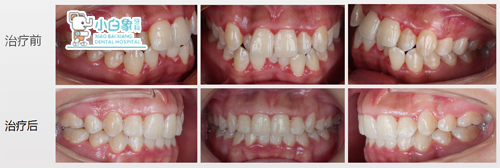

治疗前后对比